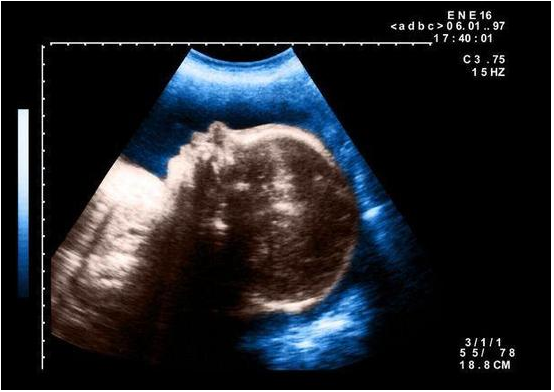

腹中胎儿

这名畸形婴儿出生在埃及东北部小镇的一家私人医院。图为该医院示意图。

据英国《每日邮报》报道,当地时间10月6日,埃及的一家私人医院El Senbellawein接生一个罕见的缺陷婴儿,他只有一个眼睛,医生检查后预测,该婴儿活不过几天。这个畸形的婴儿让人想起希腊神话中只有一只眼睛的巨人。据医生称,婴儿可能是在子宫里受到了放射物的影响。